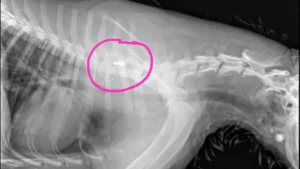

“Pudieron detectar que había una bala alojada en una de sus vértebras, así que esto es producto de un tiro que ha recibido”, explicó Luzio, quien detalló que el proyectil se observa con claridad en las radiografías.